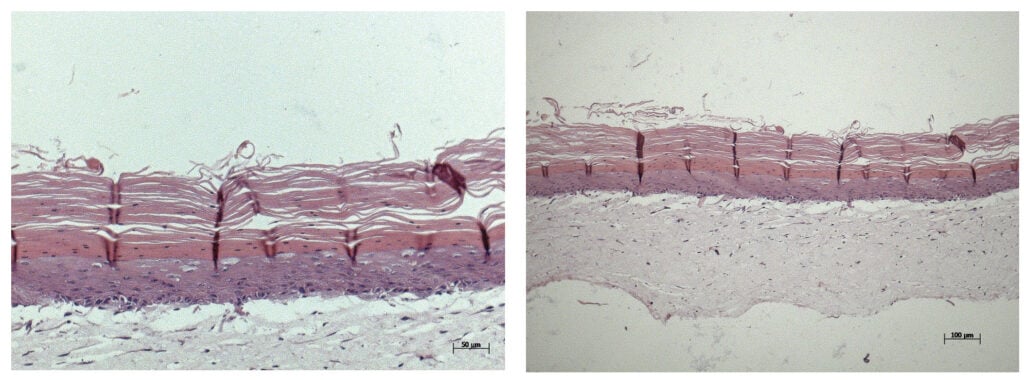

In three sets of rat studies, the researchers achieved the hypodermis and dermis layers, with the epidermis forming within two weeks, according to Ibrahim T. Ozbolat, PhD, professor of engineering science and mechanics, of biomedical engineering and of neurosurgery at Penn State, who led the study.

They also found that the hypodermis contained downgrowths, the initial stage of early hair follicle formation. According to the researchers, while fat cells do not directly contribute to the cellular structure of hair follicles, they are involved in their regulation and maintenance, according to the Penn State press release.

Figure 1 © Laboratory of Skin Physiology and Tissue Engineering of the School of Arts, Sciences and Humanities of University of Sao Paulo. Figure 2 © Michelle Bixby/Penn State. All Rights Reserved